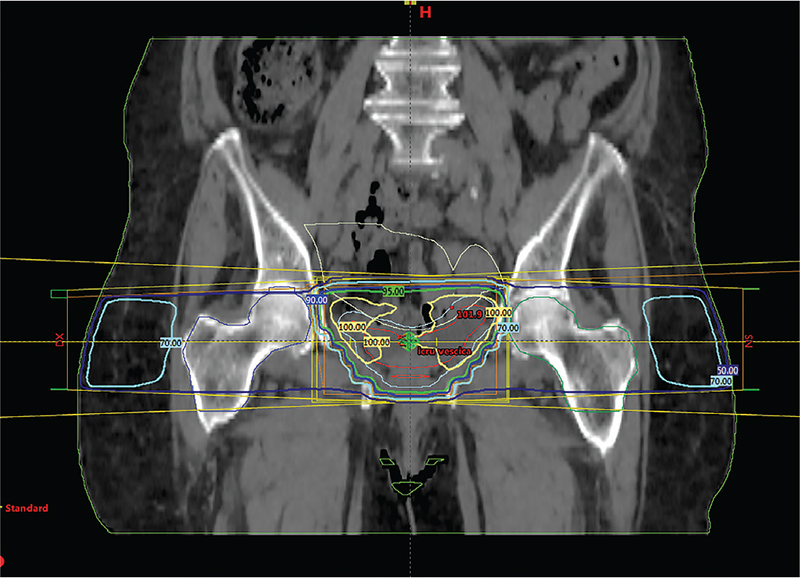

Dalle immagini sottostanti si evince come con la tecnica box, utilizzando cioè quattro fasci di fotoni con angoli di entrata ortogonali tra di loro e sistema di conformazione dello stesso fascio con utilizzo di un sistema multilamellare, posto sulla testata dell’acceleratore lineare, si abbia una notevole copertura con il massimo della dose voluta del target, in questo caso dell’intera vescica. Dalle immagini (Fig. 1 e 2) viene mostrata la riproduzione di un classico piano di trattamento rispettivamente in visione assiale e coronale utilizzando tale tecnica.

Il trattamento primario, previa TC di centratura, ha previsto l’irradiazione dell’intera vescica utilizzando fotoni X6 Mv da acceleratore lineare e tecnica box 3D conformazionale (9); sono stati erogati 20 Gy in 5 frazioni giornaliere ognuna di 4 Gy.